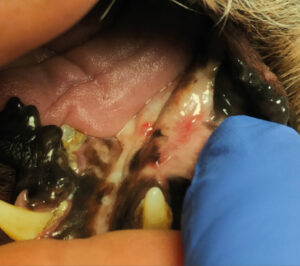

Tumores de la cavidad oral

Los tumores de la cavidad oral constituyen aproximadamente el 6–7 % de todas las neoplasias en perros y cerca del 3 % en gatos. En la especie canina, los tipos tumorales más prevalentes son el melanoma maligno, el CCE y el fibrosarcoma. En contraste, en la especie felina, el CCE representa la neoplasia oral más frecuente.

Estas neoplasias se caracterizan por un elevado grado de infiltración local, lo que condiciona un enfoque terapéutico agresivo. La cirugía y la radioterapia son consideradas las modalidades terapéuticas de elección para el control local. No obstante, en situaciones donde la intervención quirúrgica no es viable —ya sea por decisión del tutor o por limitaciones clínicas—, y cuando el acceso a la radioterapia es restringido o inexistente, la electroquimioterapia puede representar una alternativa útil para el control local del tumor (imágenes 18, 19 y 20).

El estadio clínico y una adecuada planificación terapéutica son aspectos fundamentales para el manejo óptimo de los tumores orales. En este contexto, la TC se considera una herramienta diagnóstica indispensable, ya que permite evaluar con precisión el grado de invasión tumoral y estimar la probabilidad de respuesta al tratamiento.

En otro estudio, centrado en el tratamiento del CCE oral no tonsilar, se observó una tasa de respuesta global del 90,3 %, con un 72 % de respuestas completas y un 18,2 % de respuestas parciales. Los resultados indicaron que los tumores con un diámetro inferior a 2 cm presentaron una mejor tasa de respuesta terapéutica, lo que sugiere que el tamaño tumoral constituye un factor pronóstico relevante en esta neoplasia (imágenes 21 y 22).

La electroquimioterapia puede emplearse como tratamiento primario en neoplasias orales de pequeño tamaño que no presentan evidencia de invasión ósea. No obstante, el tratamiento de lesiones localizadas en regiones más caudales de la cavidad oral suele ser técnicamente más complejo, y en aquellos casos en los que el tumor se encuentra cerca de piezas dentales, puede ser necesaria la extracción de estas para permitir una adecuada aplicación del tratamiento. Debe tenerse particular precaución en el manejo de tumores localizados en la lengua o en la región sublingual, debido al elevado riesgo de necrosis tisular y al posible fracaso terapéutico, aspectos que deben ser claramente comunicados a los tutores de los pacientes.

Además, la electroquimioterapia puede ser utilizada con fines paliativos, especialmente en el control del sangrado asociado a tumores orales avanzados. Asimismo, su aplicación en combinación con cirugía se ha explorado como estrategia terapéutica en tumores de gran tamaño, con comportamiento infiltrativo y compromiso óseo, en los que contribuye al control local de la enfermedad.